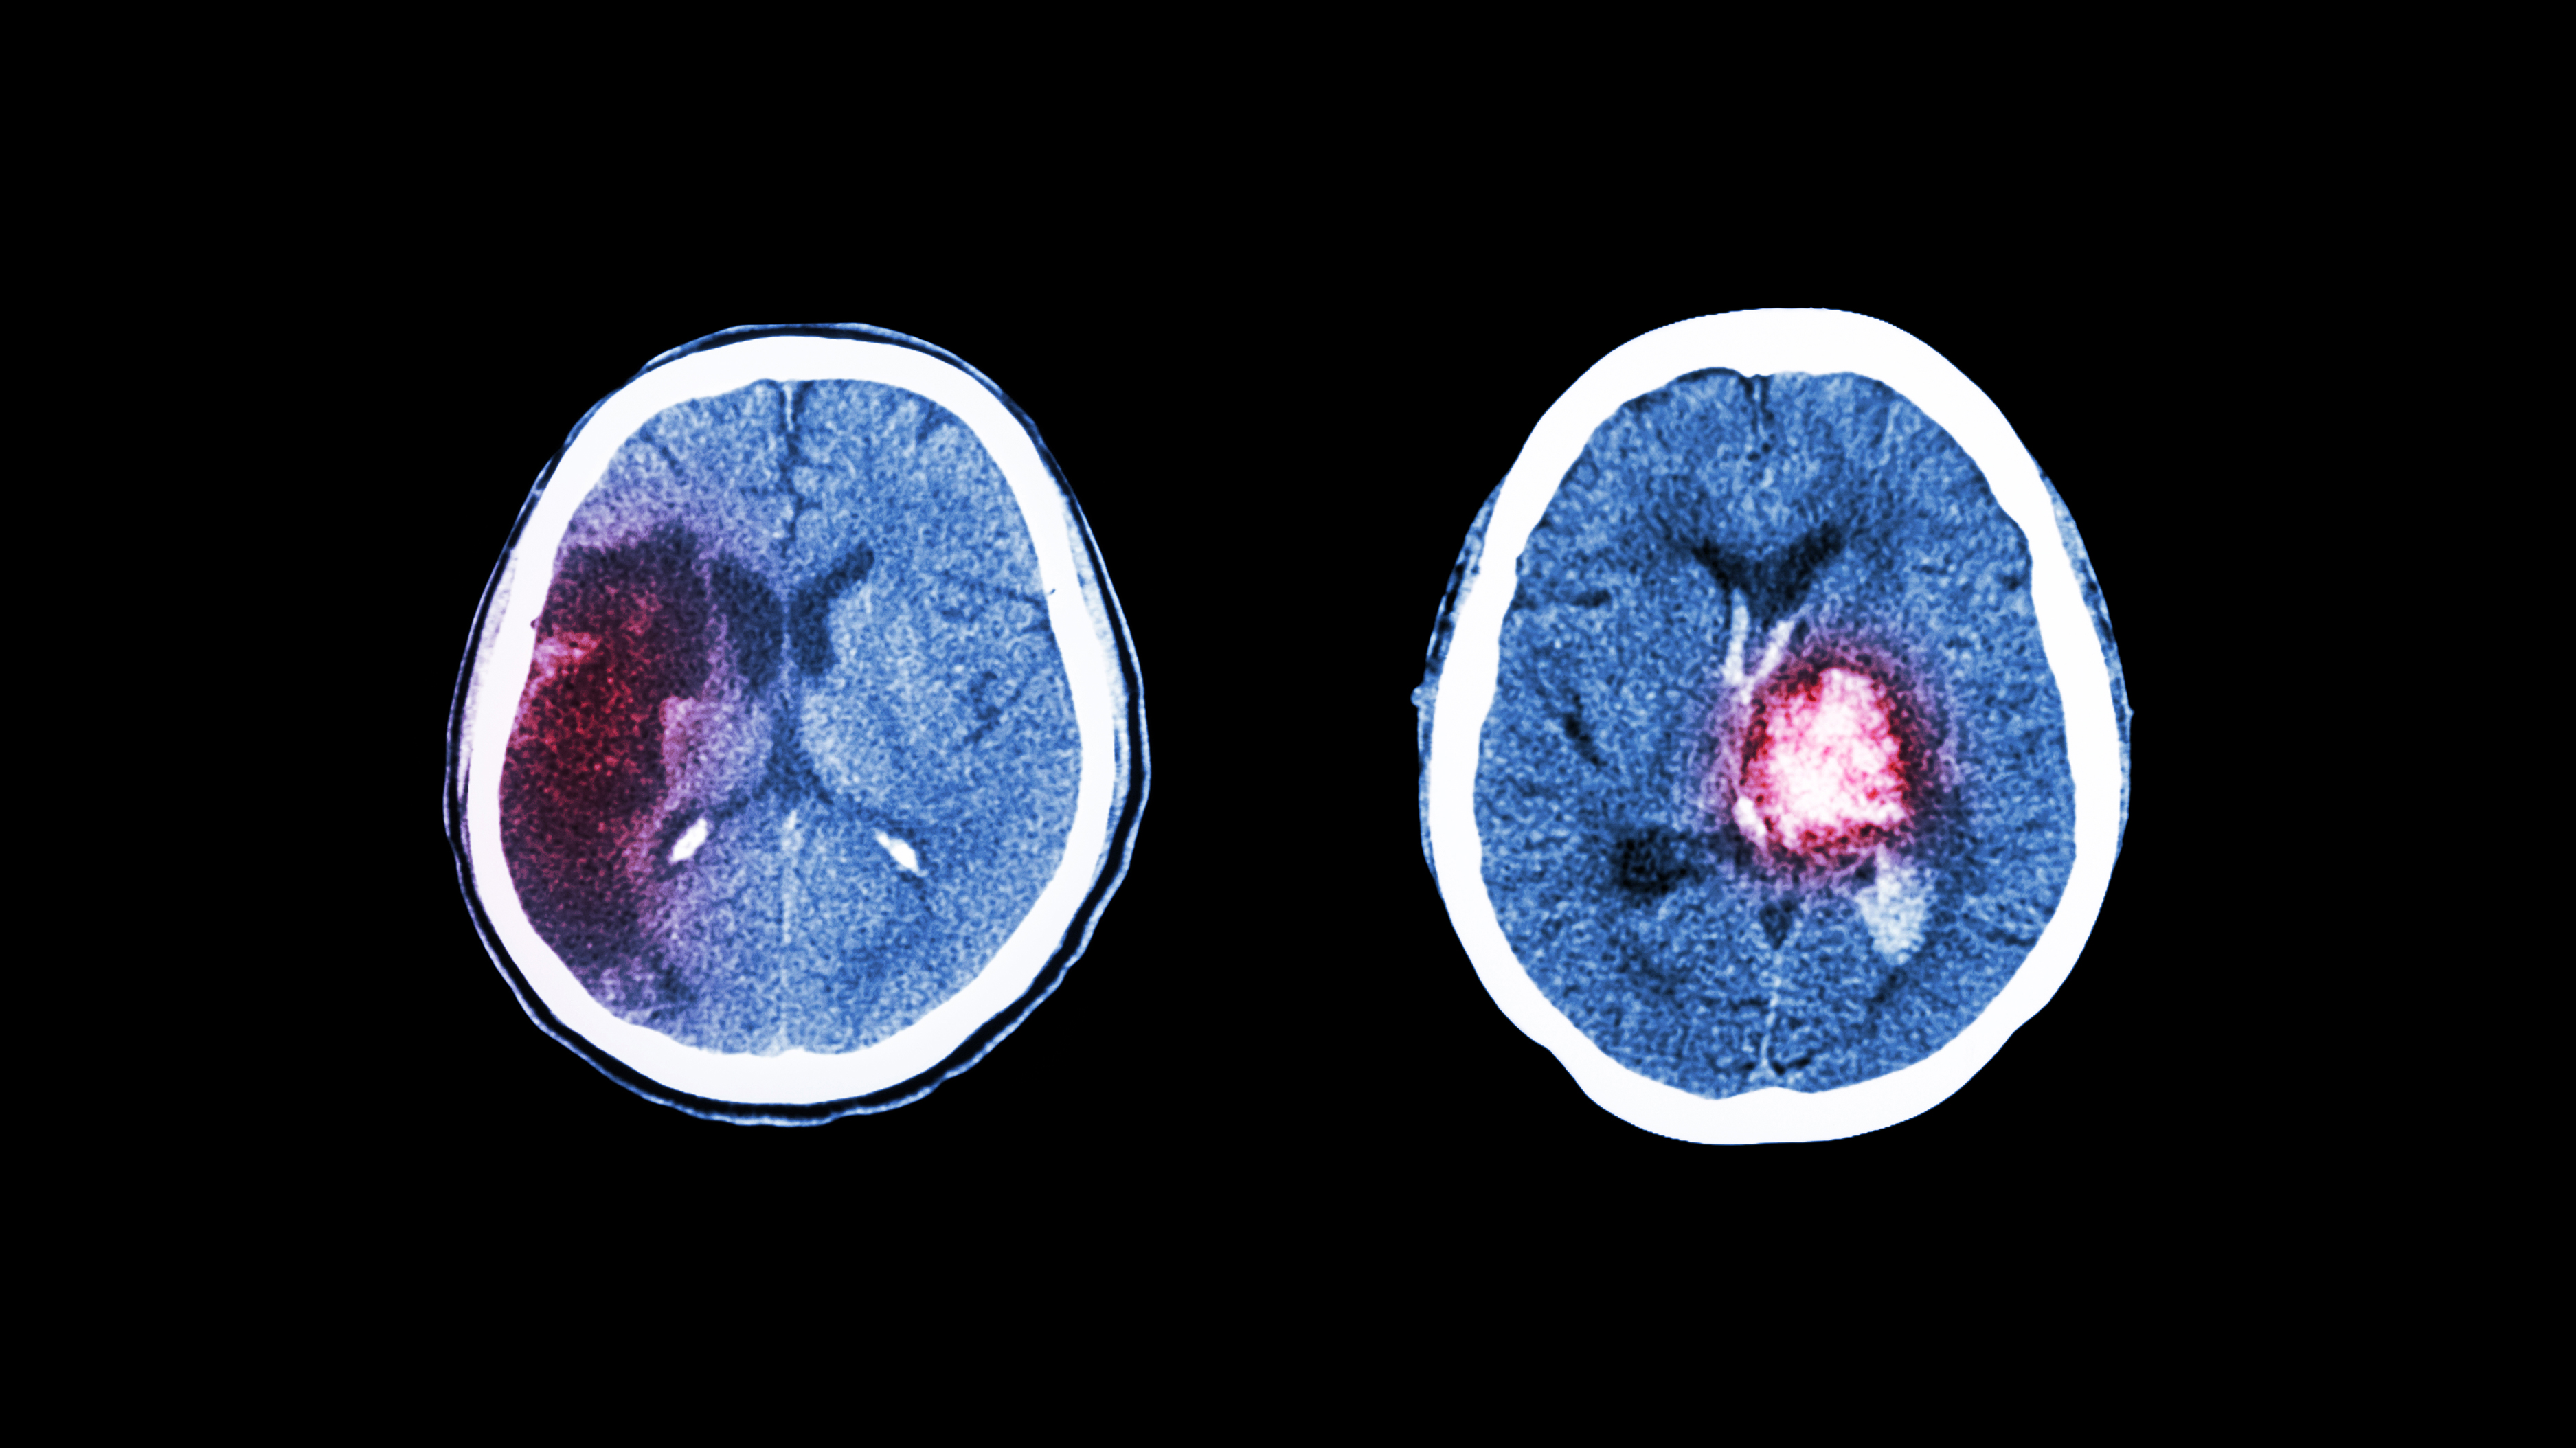

Hvert år rammes cirka 15 000 personer av hjerneslag i Norge (1). Fatigue forekommer ofte som en subjektivt opplevd tilstand etter hjerneslag ledsaget av sterkt redusert energikapasitet, kalt post-stroke fatigue (PSF) (2, 3). I den norske befolkningen opplever rundt 10 prosent utmattelse eller fatigue (4), men forekomsten av fatigue etter hjerneslag er høyere (3).

I 91 prosent av tilfellene var blodpropp årsaken til hjerneslaget, mens 9 prosent skyldtes hjerneblødning. Totalt var medianskåren for hjerneslagets alvorlighetsgrad på NIHSS 3, og interkvartilbredden gikk fra 1–6. Kun 19,3 prosent rapporterte ingen tidligere sykdommer. Det var 22,4 prosent som rapporterte om depresjon 4–6 uker etter hjerneslaget. Deltakerne rapporterte at de i utstrakt grad mottok rehabiliteringstjenester 4–6 uker etter hjerneslaget. Kun 34,3 prosent rapporterte at de ikke mottok noen form for rehabiliteringstjenester (tabell 2).